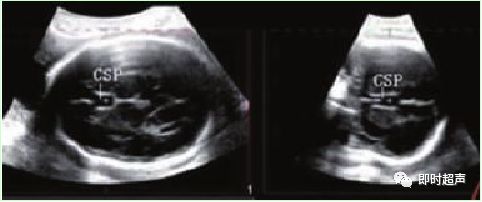

十、透明隔腔(CSP)

透明隔是两侧侧脑室间的间隔,从妊娠10~12周开始发育,由灰质细胞和神经纤维组成 的两层薄膜间的腔隙即为CSP。大多数学者认为在孕 18~37w 之间 CSP 的显示率为 100%。

看不到 CSP 或 CSP 异常增宽已经被看作先天性颅内发育异常的一个线索。包括胼胝体发育不全、全前脑、视-隔发育不全、精神障碍等。应进一步做详细的检查。

各组测量显示孕周与透明隔腔大小无相关性

超声检测CSP对胎儿神经系统诊断和鉴别诊断意义:超声检查CSP主要表现为缺失和异常增大,从而导致CSP畸形或其他颅脑畸形。透明隔、胼胝体、边缘系统有共同的胚胎起源,透明隔发育异常预示包括胼胝体、边缘系统在内的发育异常。

✔ 正常透明隔腔宽度6mm±2.64mm,宽度大于10mm为异常。

✔ 晚孕期透明隔腔的存在是胎儿脑中线结构发育良好标志。

✔ CSP缺失是产前超声诊断胼胝体发育不全的最初线索,正中矢状和冠状切面上不能显示胼胝体和CSP,第三脑室扩大上移、侧脑室增大呈泪滴状,即可诊断胼胝体发育不全。

✔ CSP 异常增大宽度超过 10mm。则可成立透明隔囊肿诊断扩张性透明隔囊肿最常见。

✔ 异常增宽的 CSP 与精神异常有关,临床表现是头痛、癫痫、昏厥、精神障碍和神经症。